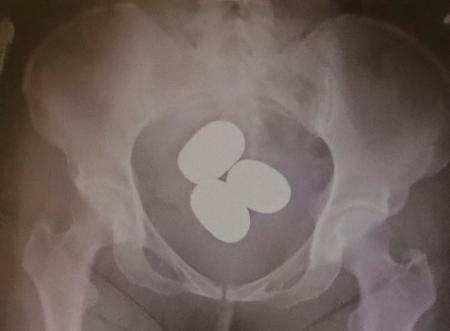

成田税関支署によると、成田空港で粉状の金の摘発は昨年1年間で23件、計約31キロ。今年は3月までに30件、計約45キロで、いずれも香港や中国籍の旅客が、粉状の金を空港到着後などに体内に隠し、持ち込もうとした。中高年の女性が多く、複数の塊に分けて約2・7キロ分を密輸しようとした男性もいたという。